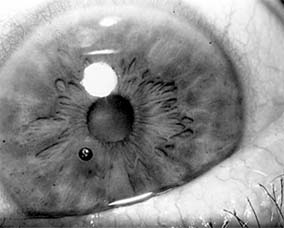

Simple corneal epithelial defects are treated with antibiotic ointment and a pressure patch to immobilize the lids. For removal of foreign matter, a topical anesthetic can be given and a spud or fine-gauge needle used to remove the material during slitlamp examination. A cotton-tipped applicator should not be used because it rubs off a large area of epithelium, often without removing the foreign body. Metallic rings surrounding copper or iron fragments (Figure 19-2) can be removed with a battery-operated drill with a burr tip. Deeply embedded inert materials (eg, glass, carbon) may be allowed to remain in the cornea. If removal of deeply embedded fragments is necessary or if there is an aqueous leak requiring sutures or cyanoacrylate glue, the procedure should be undertaken by microsurgical technique in an operating room, where the anterior chamber can be re-formed, if necessary, with or without viscoelastics under sterile conditions.

Figure 19-2

Figure 19-2: Metallic corneal foreign body. (Courtesy of A Rosenberg.)

Following removal of a foreign body, antibiotic ointment should be instilled and the eye patched. The wound should be examined daily for evidence of infection until it is completely healed.